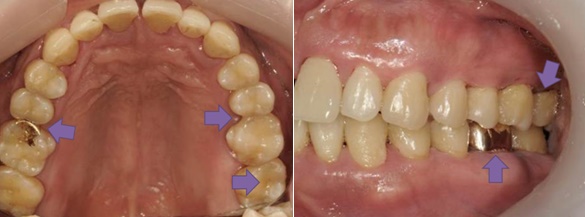

하지만 대도시에는 슬럼가가 있듯이 입속에도 세균들이 숨어 사는 공간이 아주 많습니다. 다음 사진은 나름 구강 위생관리에 자신이 있으셨던 분의 사진입니다. 잇몸도 문제이지만 아주 많은 부위에서 충치가 발생할 수 있는 위험요소를 발견할 수 있습니다. 왼쪽 화살표부터 살펴볼까요.

- 금 인레이 하방

- 어금니 사이

- 어금니 씹는 면의 고랑 (groove)

- 금 크라운

- 위 어금니와 잇몸이 맞닿는 부분

이 외에도 수많은 세균의 번식처가 될 수 있는 부분들이 있지만 가장 충치가 많이 발생하는 부분 위주로 골라봤습니다.

많은 성인 환자분들은 치아의 평평한 면만 양치질을 하는 경향이 있습니다. 정작 평평한 면은 자정작용이 활발히 이루어지기 때문에 충치가 잘 안 생긴다는 점이 아이러니하죠. 치아의 사이와 어금니의 고랑이 일차적으로 충치가 가장 많이 생기며 양치질도 잘 되지 않는 곳입니다. 하지만 예외로 5번을 보시면 위 어금니와 잇몸 사이에 노란 치태가 가득 차 있는 모습이 보이실 겁니다. 충분히 칫솔을 깊숙이 넣지 못했다는 증거이며, 언제 치아 뿌리 충치가 생길지 걱정이 앞서는 장면이죠.